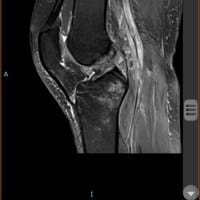

¿Es posible que tenga una Rotura de LCA o menisco?

Los ligamentos que piensas pueden estar lesionados se encuentran en la rodilla y en la imagen no se visualiza la rodilla. No puedo decir mucho más.